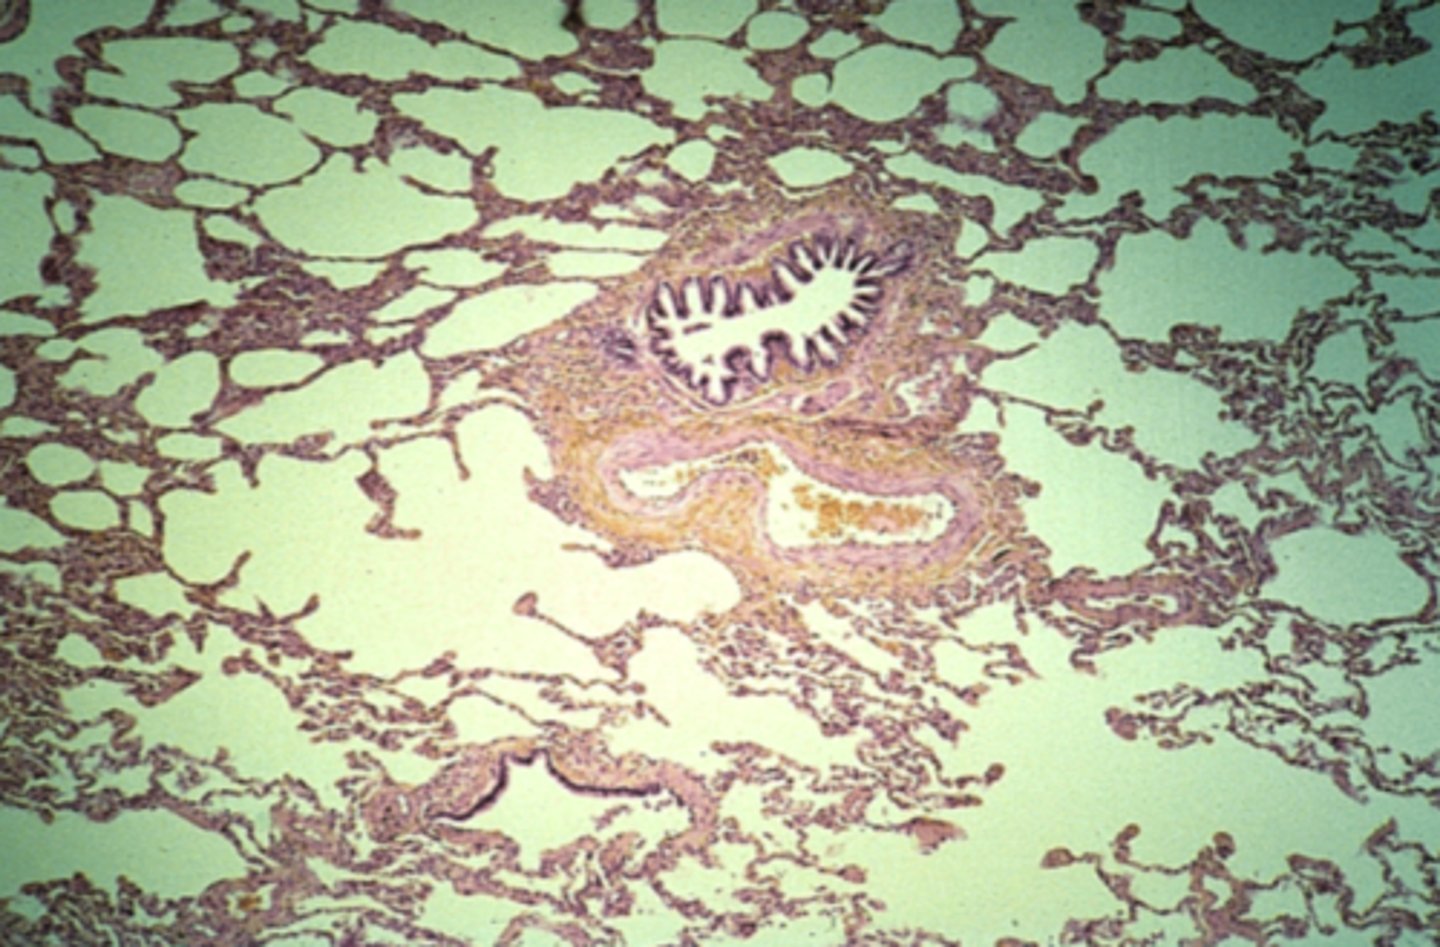

trachea

What is this?

lung

What is this?

lung

What is this?